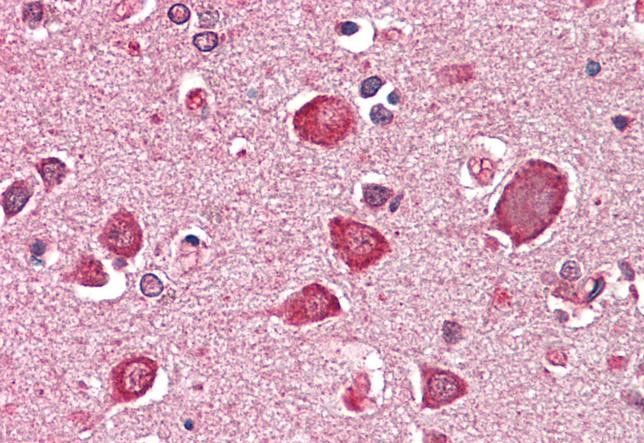

TargetGABRA6

- Target nameGABRA6

- Target descriptiongamma-aminobutyric acid type A receptor subunit alpha6

- Target synonymsGABA subunit A receptor alpha 6; GABA(A) receptor subunit alpha-6; GABA(A) receptor, alpha 6; gamma-aminobutyric acid (GABA) A receptor, alpha 6; gamma-aminobutyric acid receptor subunit alpha-6; gamma-aminobutyric acid type A receptor alpha6 subunit